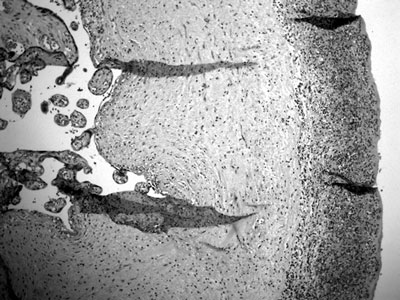

Εικόνα 2. Παρουσία μακροφάγων στους υμένες που έχουν φαγοκυτταρώσει αιμοσιδηρίνη (Χρώση Perl. Αρχική μεγέθυνση 100).

Το παλαιότερο αιμάτωμα ορισμένες φορές μπορεί να τεκμηριωθεί μικροσκοπικά από την παρουσία των μακροφάγων στους υμένες που έχουν φαγοκυτταρώσει αιμοσιδηρίνη (εικόνα 2) και από τις εναποθέσεις ινικής στον βασικό φθαρτό. O όρος χρόνια αποκόλληση (chronic abruption) του πλακούντα χαρακτηρίζεται από τη διάχυτη αιμοσιδήρωση των υμένων. Η χρόνια αποκόλληση υποδηλώνει αιμόρροια 1ου και 2ου τριμήνου της κύησης και θεωρείται παράγοντας κινδύνου για νευρολογικές διαταραχές του νεογνού.(11)